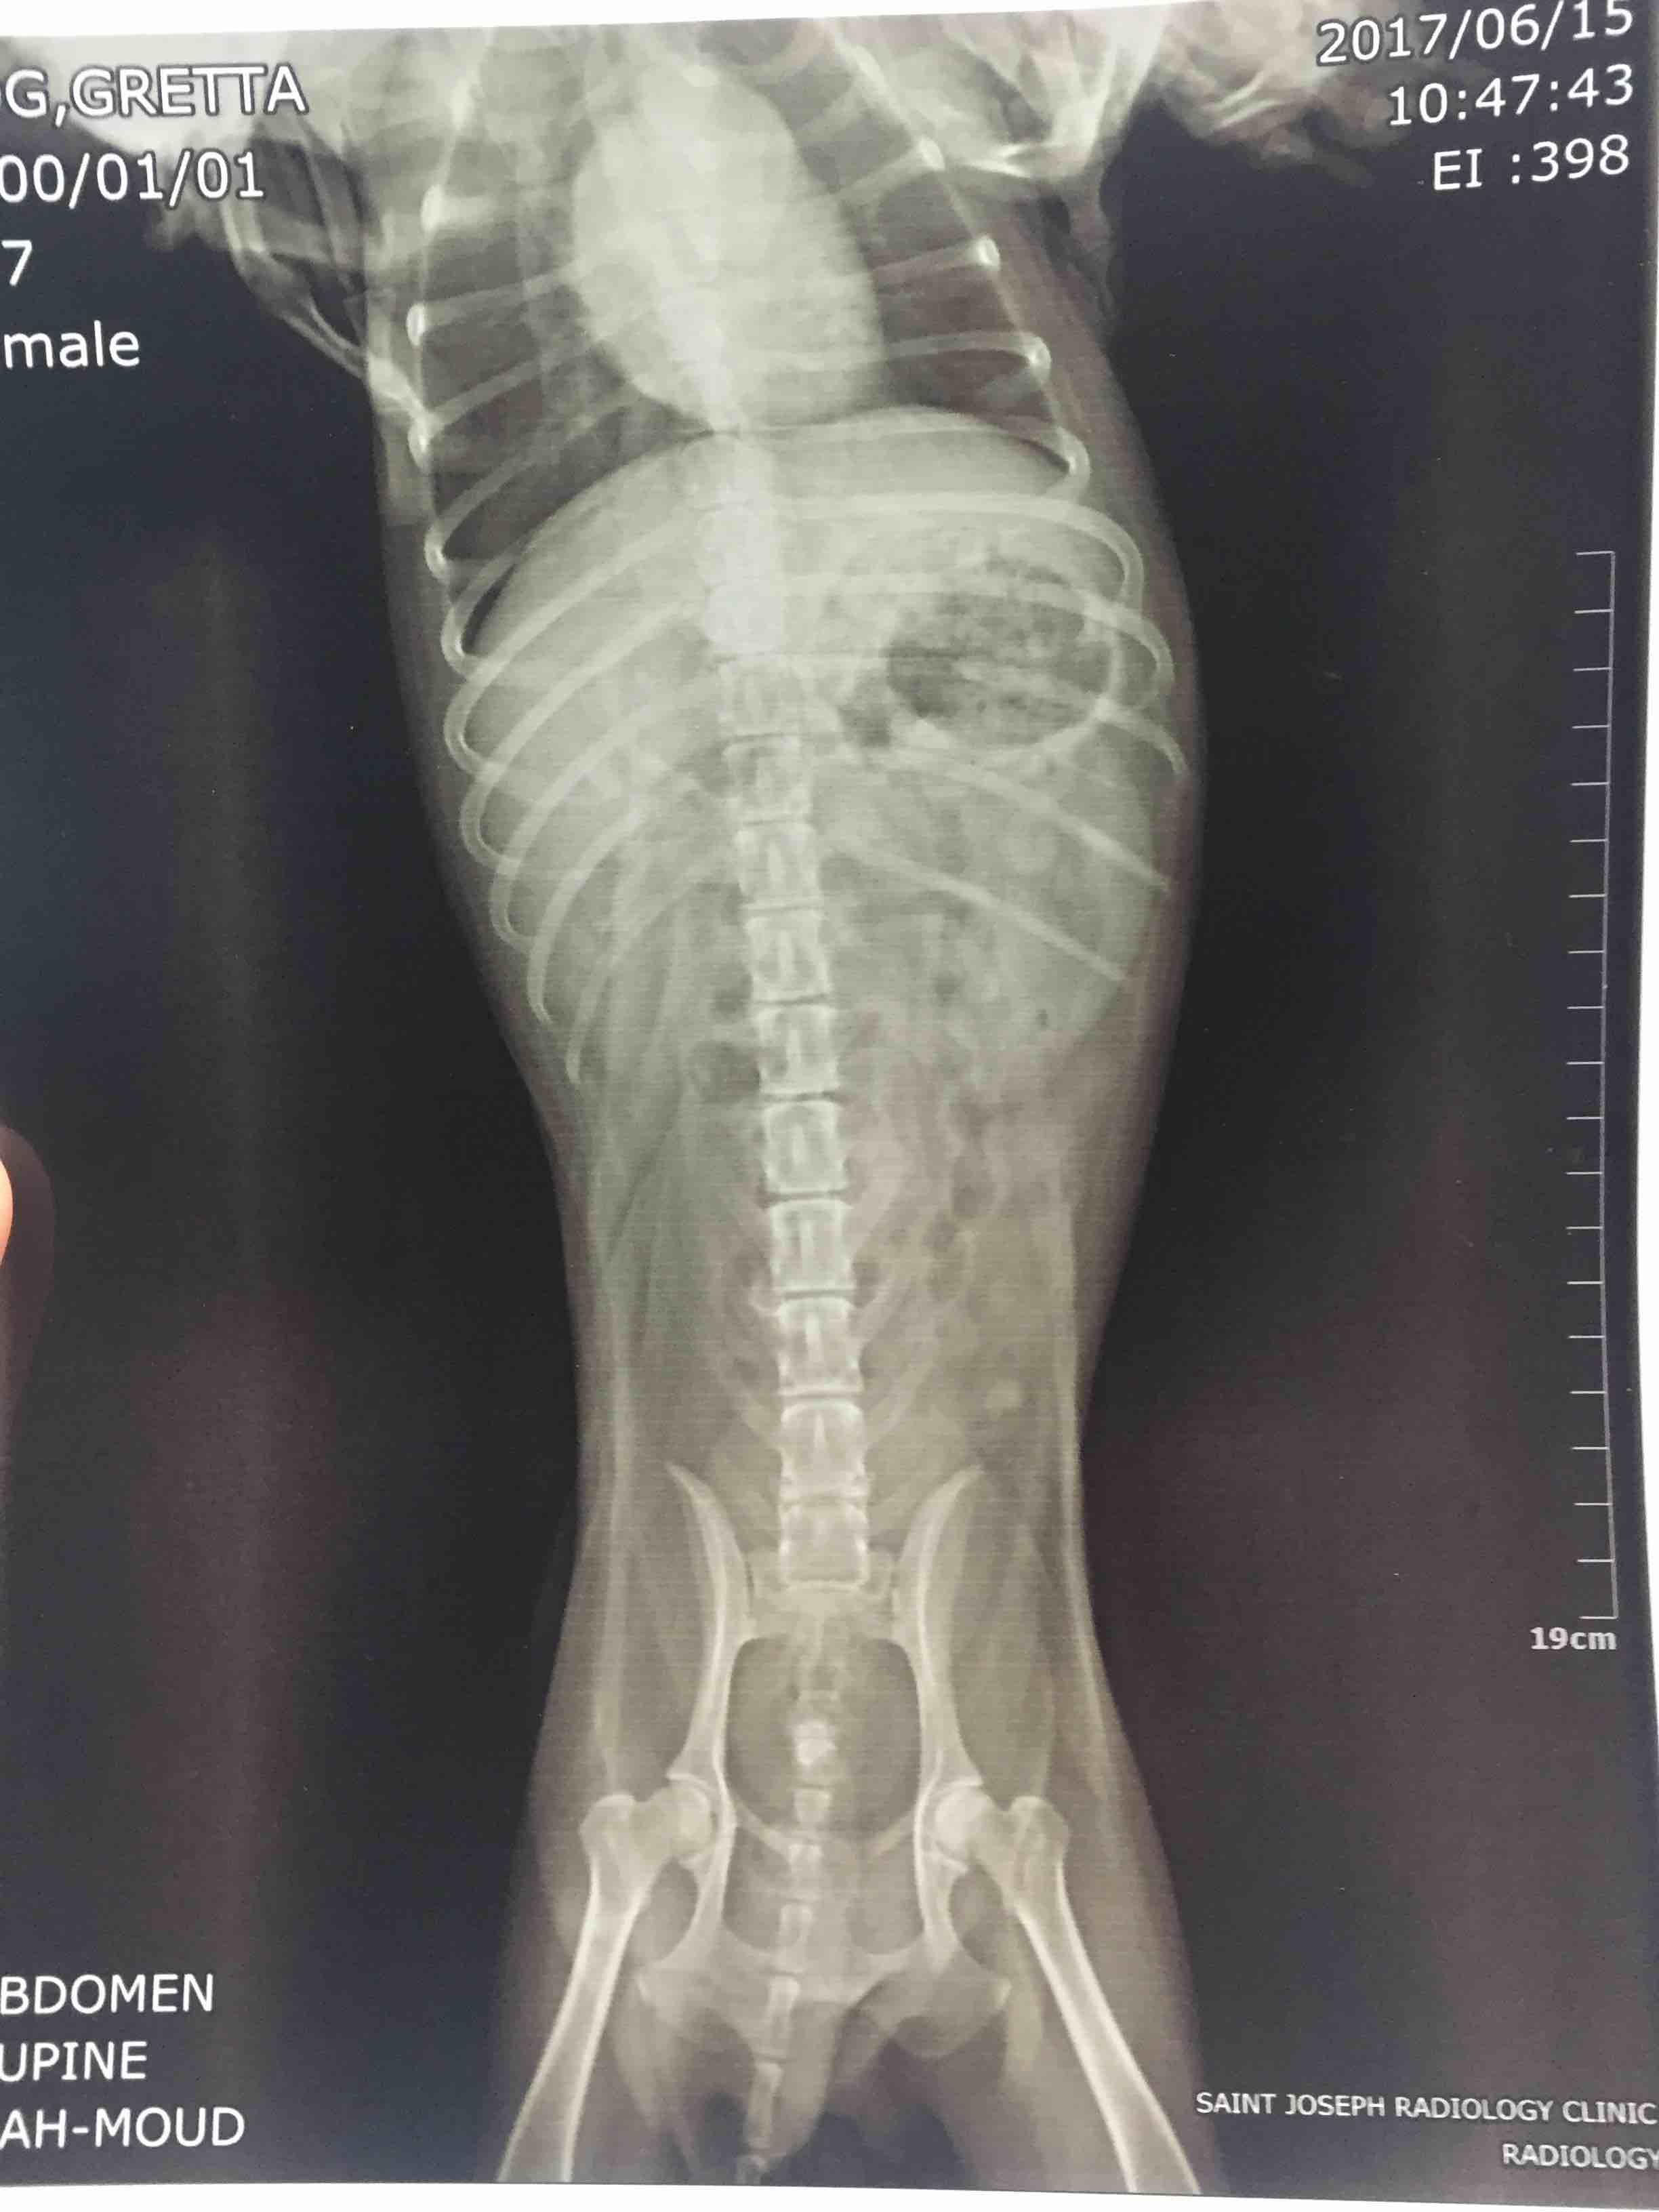

Hi. I just had my dog x-rayed again. I want to ask for your opinion regarding the encircled part of the xray.. do you think this is normal? I know theres a stone in the bladder but i'm curious about that thing i encircled.. my vet says its fine but im still curious. Is it just gas? Theres no other way to look closely because ultrasound is not available here in my city. Thanks

Unfortunately the quality of the image coming through to us isn't great. If you are talking about the circular area on the upper right side of the abdomen, this is gas in the stomach and can be normal. If your vet wants to try additional diagnostics but doesn't have ultrasound, they could do a barium study, or they could send the x-rays to a radiologist for review (a veterinary radiologist has extensive training at reviewing x-rays and so can sometimes interpret things a regular vet may not). X-rays can be send electronically to a radiologist for review through various services, so I would ask them if they feel either of these options would be appropriate.